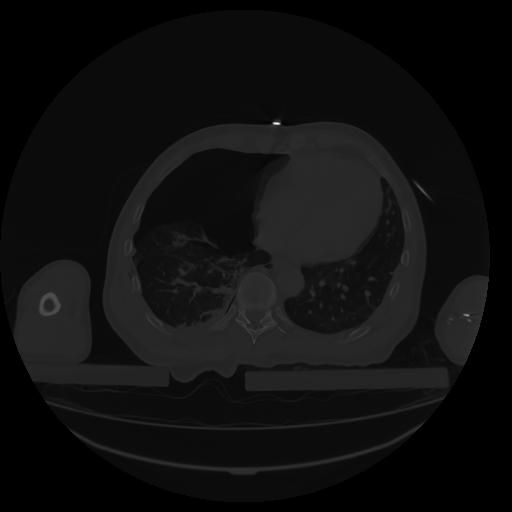

27 CUERPO,CE,Axial,3.0,CUERPO,,